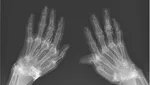

Jakarta - Belum lama ini heboh gambar rontgen penemuan benang 'susuk' emas di dalam tubuh seorang pasien di Korea Selatan. Ternyata, ini bukan kejadian yang pertama.